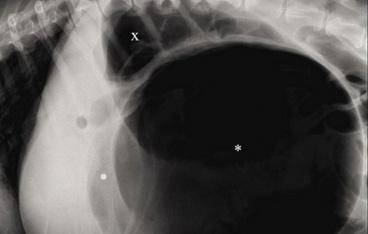

2 globulinas: 14,8 g/l, ref: 4-9 g/l) y disminución de las beta-globulinas (beta-globulinas: 8,1 g/l, ref: 9-19 g/l). Se realizó una ecografía abdominal en la que se observó abundante líquido libre abdominal y la presencia de una masa heterogénea en la zona pancreática, además del incremento de la ecogenicidad y aspecto heterogéneo del peritoneo, lesiones nodulares hepáticas, y efusión pleural escasa (Figs. 2 y 3).

Figura 2. Presencia de líquido libre abdominal (*).

Figura 3. (A) Masa abdominal (*) asociada a la zona pancreática (P). (B) Masa abdominal de grandes dimensiones (*) y líquido libre abdominal.